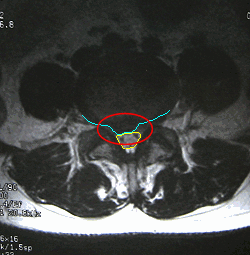

水平断面

■水平断面

少し見にくいのですが、中央やや左(患者さん右)に飛び出しているのが、見られます。